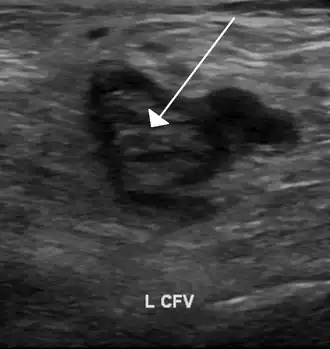

An ultrasound image demonstrating a blood clot in the left common femoral vein. | |